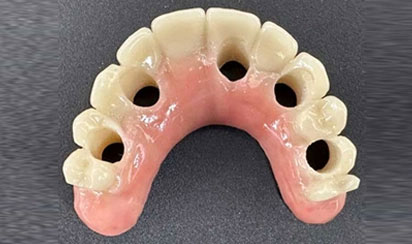

For your final teeth, you, the dentist, and our in-house lab technician will work together to design your perfect smile. While other offices still use acrylic denture teeth over titanium bars, we use zirconia for the best in appearance, durability, and resistance to staining. Upgrading to these materials usually costs significantly more at other offices. At Sumner Dental Group, they’re our standard.

Custom-Made (OUR)

Match to Existing Natural Gum Tissue

Retrofitting (Others)

Counter-Top Teeth

Bulky Teeth